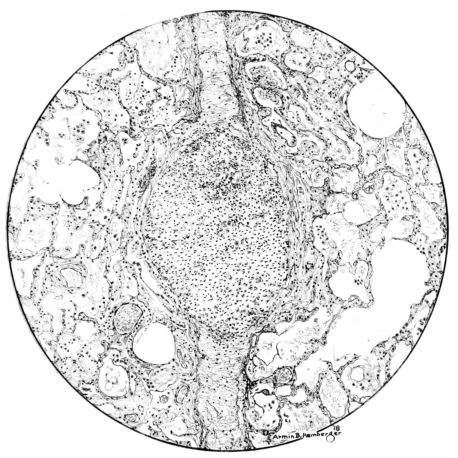

FIG. IV. AUTOPSY NO. 205. CONGESTION AND EDEMA OF THE SUBMUCOSA AND REGENERATION OF THE TRACHEAL EPITHELIUM.

The changes are less marked, perhaps, in the trachea than in its finer ramifications. The mucosa is constantly more or less destroyed and large areas, usually focal, are entirely devoid of their epithelial covering. This is replaced by a sparse exudate, composed largely of red blood cells, mucus, a small amount of fibrin, and nuclear fragments (Fig. II). It may dip into the submucosa for a short distance, but usually these indentures are associated with the ducts of the mucous glands into which the inflammatory reaction extends. A more striking feature than the exudate, however, is the edema and the congestion of the submucosa. The loose areolar tissue of the submucosa is spread widely apart, and throughout it distended blood vessels are very conspicuous. Occasionally such a vessel is broken and actual hemorrhage appears in the submucosa. Occasionally, too, the inflammation extends down the duct to the mucous gland itself, and here, also, aplastic inflammatory reaction is evident, inasmuch as the acini now stain intensely red with the cells undifferentiated from each other and specked here and there by broken remains of the dead nuclei (Fig. III). After the disease has continued for a short period, even at the end of five or six days, some regeneration of the epithelial lining may be seen (3) (Fig. IV). But despite this, the acute picture persists, and there goes on, side by side, an attempted repair characterized by epithelial regeneration and the same evidence of acute change. Since the lesion is essentially a superficial one, scars or contractures of any extent are not encountered in the trachea, even in examples of the disease that have ended fatally only after many weeks.[4]